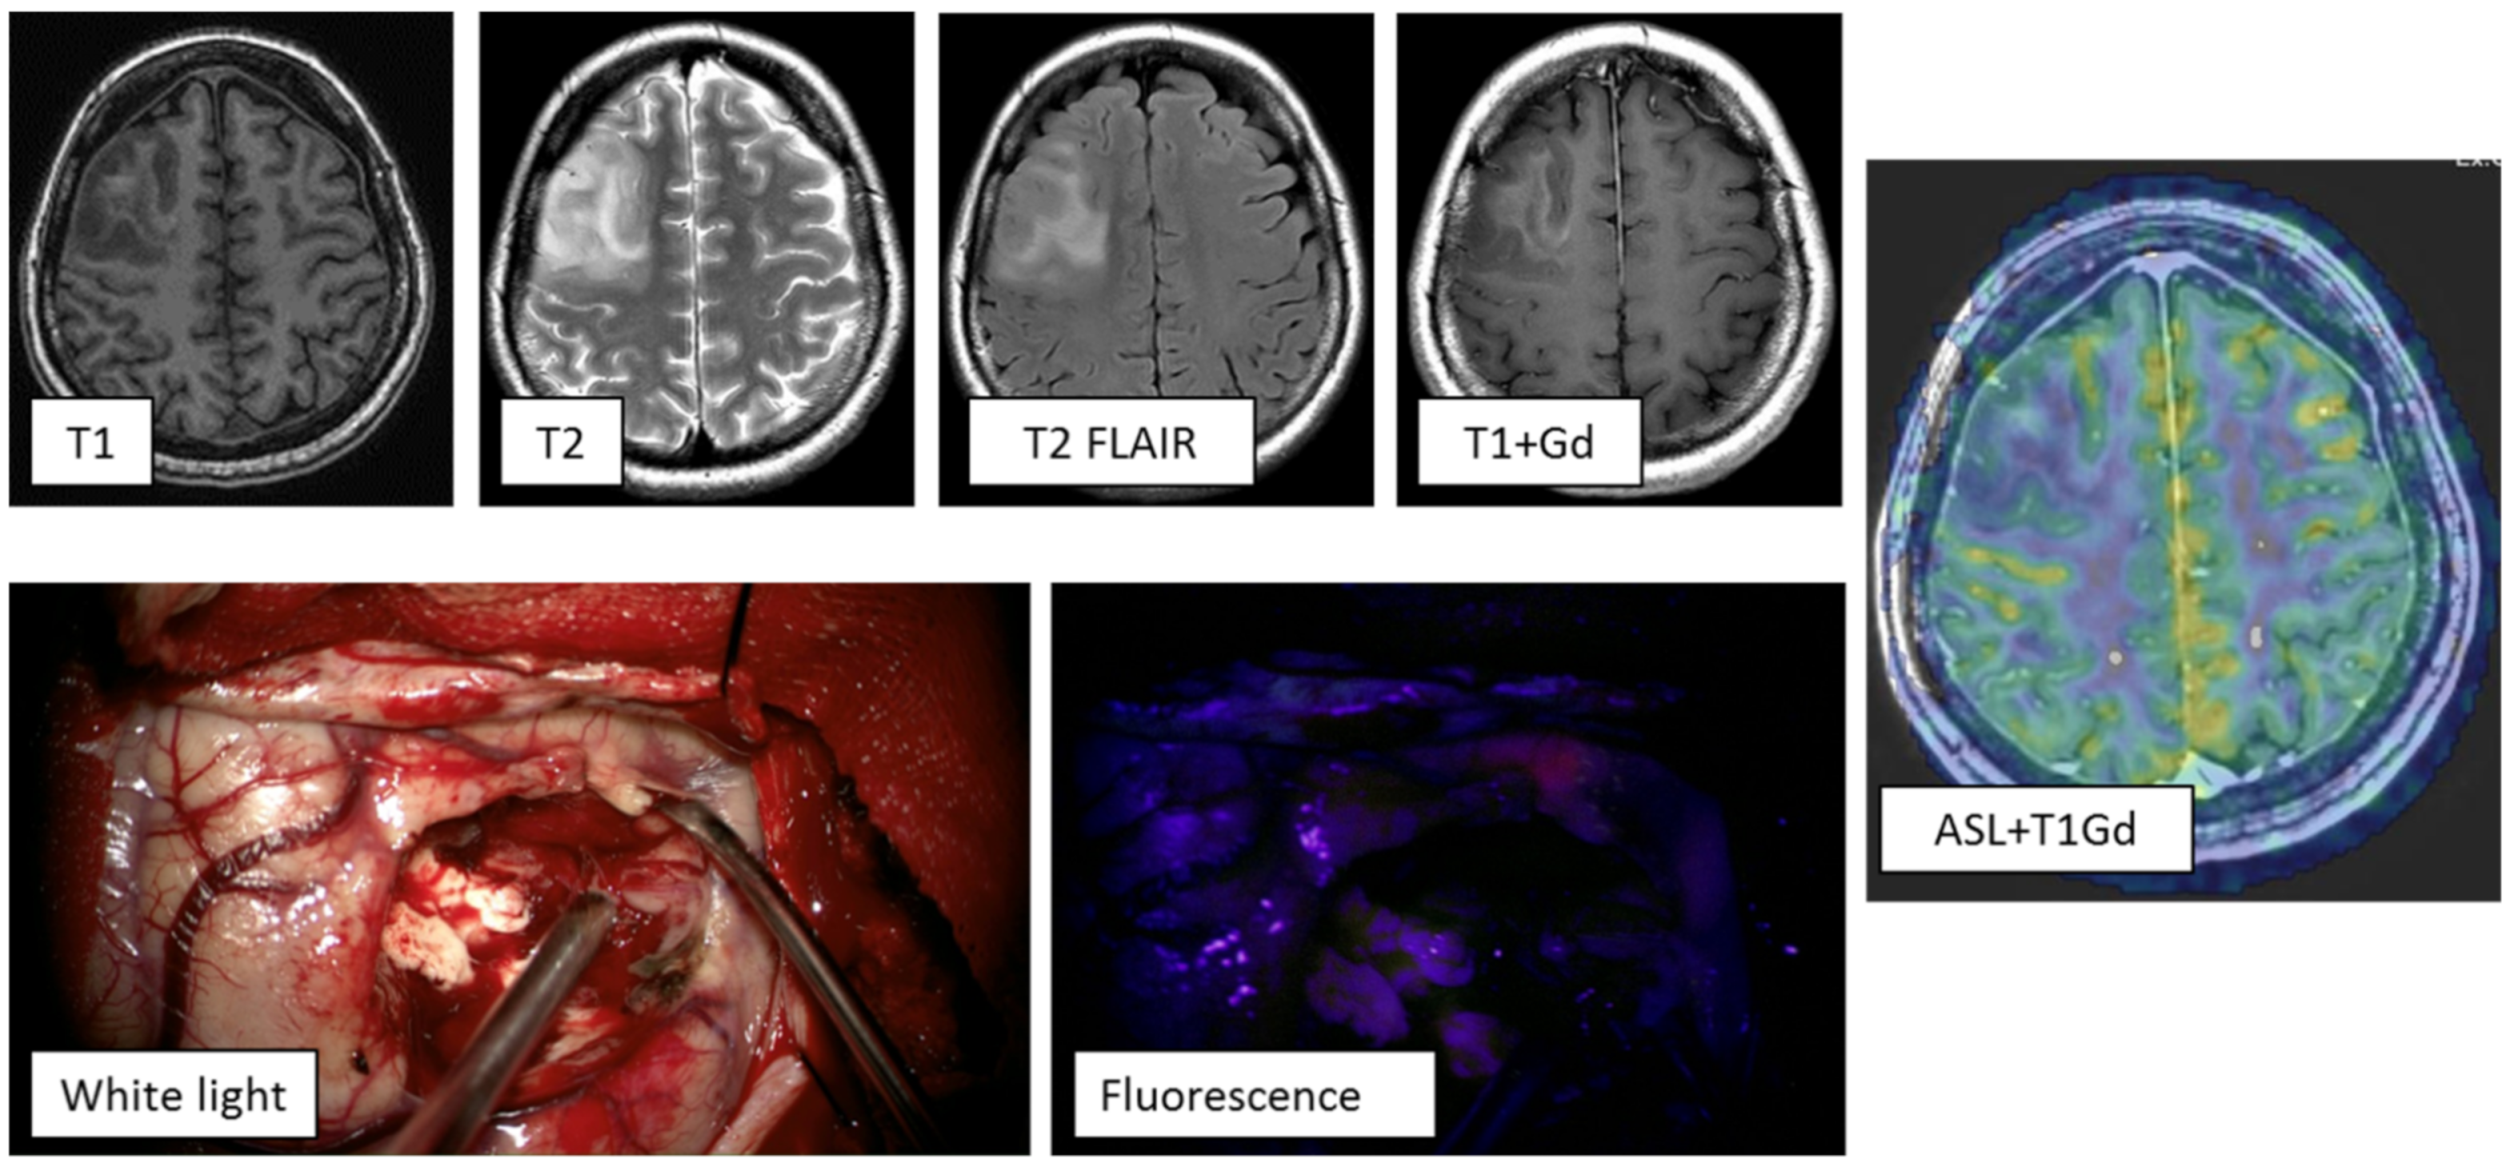

Clinical case 1: A 61-year-old female with symptoms of motor aphasia. MRI study demonstrated a left frontal lobe intracerebral lesion with central necrotic changes and increased pathological contrast enhancement mainly in the peripheral parts of the tumor. ASL perfusion revealed high tumor blood flow (TBF up to 289.7 mL/100 g/min). Another hyperintense lesion on T2 and T2-FLAIR was present in the right basal ganglia without any signs of pathological enhancement. On the basis of the clinical and radiological data, multiple primary glioblastomas were diagnosed (Figure 3). The tumor of the left frontal lobe was removed using intraoperative fluorescence diagnostics. Intraoperatively, the tumor showed intense fluorescence, facilitating radical tumor removal (the entire visible part of the tumor was removed. Histological diagnosis: NOS glioblastoma).

Figure 3. MRI study of a patient with multiple primary glioblastomas. ASL perfusion in the tumor of the left frontal lobe revealed areas of hyperperfusion: TBF = 289.7 mL/100 g/min. Tumor demonstrated vivid contrast enhancement. During surgery using fluorescence diagnostics, this tumor showed an intense glow. Gd—gadolinium.